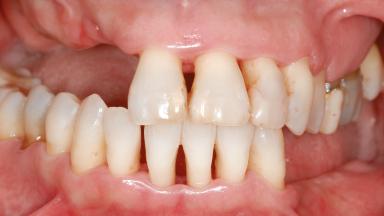

A 46-year-old woman was referred for treatment whose main complaints were mobility of her fixed partial dentures (right maxilla and left mandible) and periodontal bleeding during function. She also reported having taken systemic antibiotics to treat recurrent swelling in the area of the upper left molars. The patient had not seen a dentist for at least 2 years. She did not smoke and had no history of major systemic disease other than two minor orthopedic procedures some years back. The first-visit examination revealed poor plaque control, tooth mobility, periodontal disease, and a residual dentition widely associated with deep periodontal pockets.

Prosthesis Type FDP

Defining Characteristics Up to three missing teeth to be replaced with an implant-borne restoration or restorations